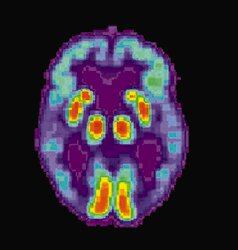

El científico explicó que hay trastornos en los que el cerebro se reduce, esto pasa con el alzhéimer.

“En el alzhéimer, ciertas regiones del cerebro en particular se encogen, las que tienen que ver con la memoria. Y uno tiene ‘huecos’ dentro del cerebro, que son las ventrículas, que se engrandecen o se alargan y esto es porque se está perdiendo masa de tejido y gran parte de esa masa que se está perdiendo son lípidos”, expresó.